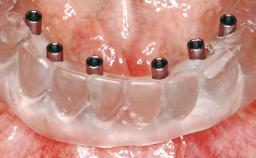

Immediate Loading of Eight Implants in the Maxilla and Six Implants in the Mandible and Final Restoration with Three-Unit and Four-Unit FDPs

Extensive scientific evidence has confirmed that immediately loaded implants with fixed full-arch provisional restorations can osseointegrate with success rates similar to conventionally or delayed loaded implants. A number of immediate-provisionalization techniques for edentulous jaws have been described. Some protocols differ when it comes to prefabricated provisional templates versus complete denture conversion; intrasurgical impressions versus direct relining; and cemented versus screw-retained provisional restorations. In this context, complete-denture conversion has been proposed for either intrasurgical impressions or direct relining. Another possibility is the utilization of a prefabricated provisional to be adapted either in the mouth (by direct relining) or in the laboratory (on a working model obtained from an intrasurgical impression).

Modality 6+ implants with immediate loading

Loading Protocol Immediate